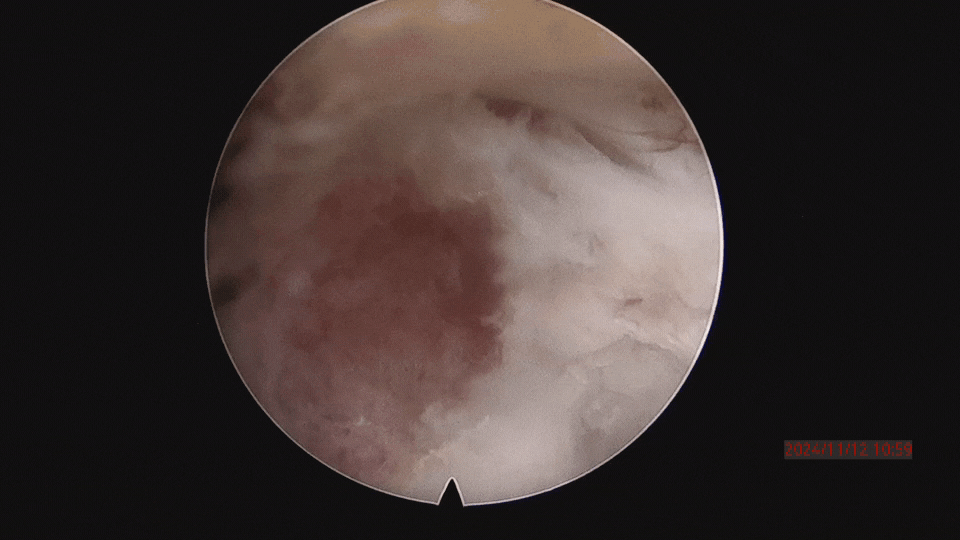

▲取骨塊的過程。